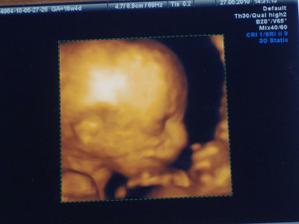

12.4.2010 - kontrola, USG - Junior ma 2,8cm a mavalo ruckami 🙂))))

27.4.2010 - USG (kombi testy) v poriadku Junior meria 5,9m 🙂

15.06.2010 - USG v nemocnici v RA, Junior je v poriadku- uff CHVALABOHU

06.07.2010 - rano opat spinenie, ale nejdem do nemocnice pokial nekrvacam, musim lezat, a dnes na USG nam ddr. Dankovcik povedal ze miminko je v poriadku a ze to bude SYN 🙂)))

08.07.2010 - v nemocke ultrazvuk, Junior aj placenta je OK, spinenie prestalo

09.09.2010 - prietoky a vsetko je OK, to mam radost. Junior vazi necelych 1700g a je krasny baculaty